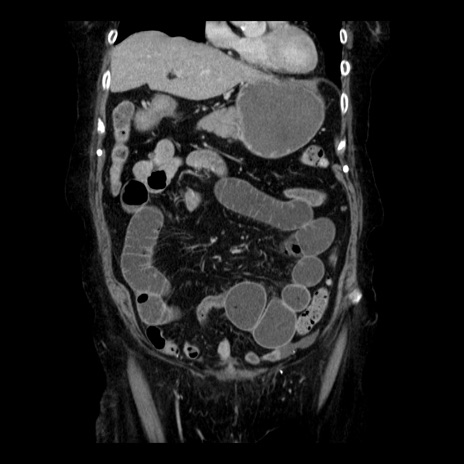

横断像

【症例】 90歳代女性

【主訴】 腹痛・嘔吐

【現病歴】今朝から左側腹部痛を認めた。 経過観察していたが、嘔吐を認めたため来院。

【既往歴】 子宮癌術後

【身体所見】 意識清明、BP 127/54mmHg、P 98bpm Sp02 95%(RA)、BT 35.8°C、腹部平坦・軟腸ぜん動音聴取良好、右下腹部圧痛(+) 反跳痛なし

【データ】WBC 9800、CRP 0.46